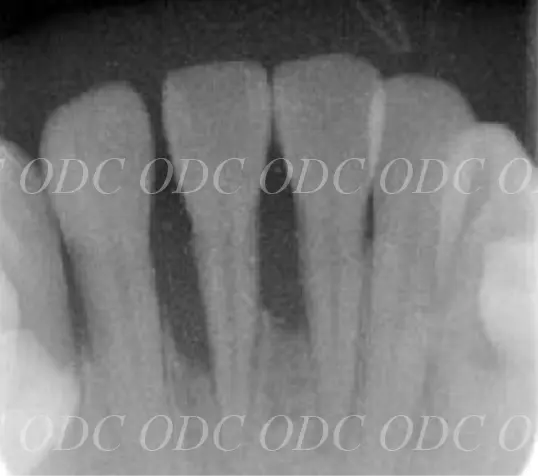

2006年

初診時

下の前歯がぐらぐらでした

2007年

歯周病

初期治療後

2006年、前歯がぐらぐらで近医にて抜歯と診断されインプラント治療を希望して来院されました。

徹底的な歯周病の治療を行なった後に、噛み合わせの先生に『噛み合わせがずれている』とご指摘を受け、噛み合わせの治療をお願いいたしました。